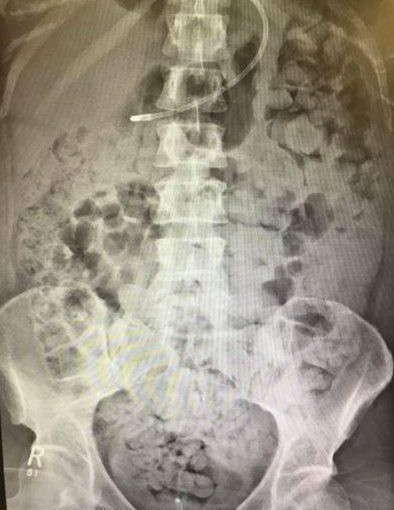

Đầu tháng này, Kelly đã đăng tải lên mạng xã hội một bức hình chụp lại kết quả chụp X-quang cho thấy chất thải phủ kín ngực, cơ hoành và phổi của cô ấy.

| Ngực của Kelly Yeoman chứa đầy chất thải sau khi bác sĩ phẫu thuật làm hỏng ruột của cô. Ảnh: The Sun. |